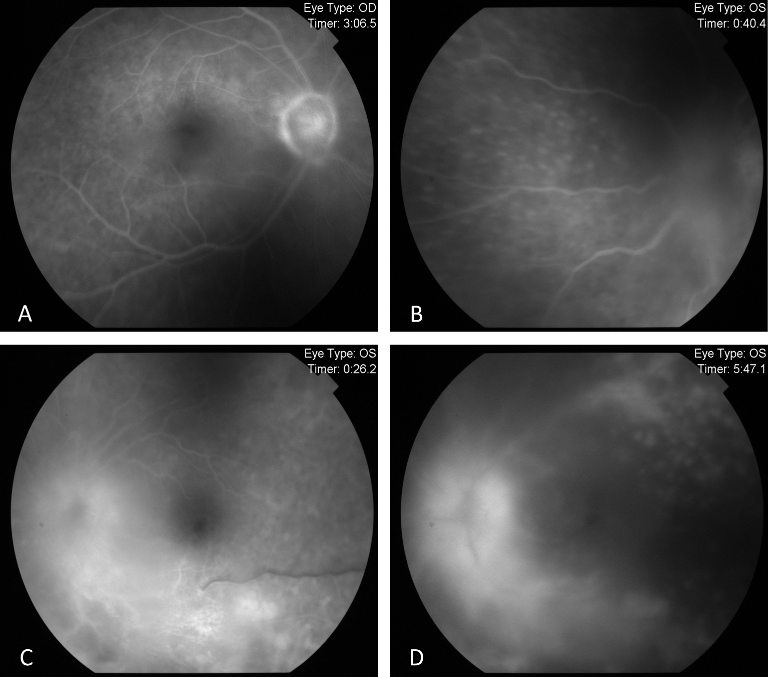

Since the visual acuity decreased to hand motion during systemic investigations, systemic steroid treatment was initiated with isoniazid (INH) prophylaxis. Following treatment, the vitreous inflammation in the left eye improved from +4 to +2 cells, allowing improved visualization of the posterior segment. The optic nerve appeared hyperemic and infiltrated, and the retina demonstrated diffuse white infiltrates with associated generalized retinal thickening, vascular sheathing, and venous beading, predominantly in the left eye (Figure 2 [Fig. 2]). Optical coherence tomography (OCT) showed irregularities and multiple subretinal hyperreflective deposits in the retinal pigment epithelium and Bruch membrane level, which were predominantly present in the left eye and severe optic disc edema (Figure 3 [Fig. 3]). Fundus fluorescein angiography (FFA) revealed indistinct granular changes and mild disc staining in the right eye. Active lesions were characterized by a typical early hypofluorescent pattern observed in the retinal infiltrates, with late hyperfluorescence containing dilated retinal vessels, diffuse pinpoint leakage at the infiltrative border in the left eye and areas of capillary dropout were observed (Figure 4 [Fig. 4]).

Figure 4: Pre-treatment FFA images

FFA exhibited indistinct granular hyperfluorescence and mild staining in the optic nerve of the right eye (A). In the left eye, FFA revealed early and dense leakage in the optic nerve, accompanied by venous segmentations, generalized granular hyperfluorescence, vasculitis, and areas of capillary dropout (B–D).